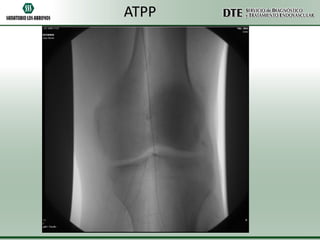

ATPP

•Utilizando una guía hidrofílica de 0.035” se atravesó la obstrucción total crónica y

sobre la misma guía se avanzó un catéter cobra 5F el cuál fue posicionado a nivel del

tronco peroneo.

•Se realizó un test angiográfico a dicho nivel, no comprobándose permeabilidad. No

se visualizaron el llenado de las arterias tibial anterior, tibial posterior ni peronea.

•Se intercambió la guía hidrofílica por una guía de 0.014” y utilizando un catéter de

trombo aspiración Export 6F, se realizó trombo aspiración mecánica a nivel del

segmento ocluido.

•Se logró aspirar gran cantidad de material trombótico fresco, a pesar de lo cuál no

pudo recanalizarse exitosamente la obstrucción total.

•Debido al riesgo de comprometer con microembolias la circulación colateral, se

decidió dar por terminado el procedimiento.

•El control angiográfico final demostró una sensible mejoría a nivel de la circulación

colateral con un llenado más rápido de la arteria pedia y el arco plantar.

ATPP •Utilizando una guíahidrofílica de 0.035” se atravesó la obstrucción total crónica y sobre la misma guía se avanzó un catéter cobra 5F el cuál fue posicionado a nivel del tronco peroneo. •Se realizó un test angiográfico a dicho nivel, no comprobándose permeabilidad. No se visualizaron el llenado de las arterias tibial anterior, tibial posterior ni peronea. •Se intercambió la guía hidrofílica por una guía de 0.014” y utilizando un catéter de trombo aspiración Export 6F, se realizó trombo aspiración mecánica a nivel del segmento ocluido. •Se logró aspirar gran cantidad de material trombótico fresco, a pesar de lo cuál no pudo recanalizarse exitosamente la obstrucción total. •Debido al riesgo de comprometer con microembolias la circulación colateral, se decidió dar por terminado el procedimiento. •El control angiográfico final demostró una sensible mejoría a nivel de la circulación colateral con un llenado más rápido de la arteria pedia y el arco plantar.